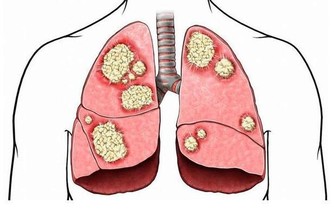

對於治療中西醫束手無策的痛風,卻有令人無法想像的療效,只要早晚飲用一顆新鮮椰子水,即使痛風情況嚴重到骨關節變形,依然可以康復。

許多患者只有血清尿酸鹽濃度的增高而沒有臨床症狀,只有在發生關節炎時才稱為痛風。痛風的病理基礎是高尿酸血症,正常人血尿酸值是男性2.4-7mg/dL,女性1.6-5.2mg/dL。

當體液中尿酸濃度超過此值時,將因過剩而在組織中沉積,這種尿酸鹽的結晶沉積在關節滑膜、關節骨、軟骨而導致痛風性關節炎,沉積在皮下則形成痛風石。中西醫均會要求痛風患者不可以攝取高普林食物,然而這些食物可以說是最起碼的美食,要痛風病患完全不吃這些食物,說真的,這種治療的犧牲代價還不小呢!